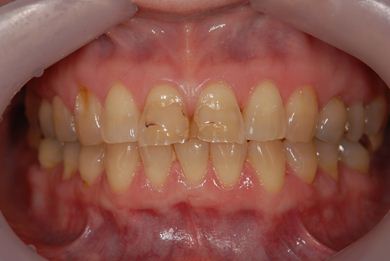

性別/年齢 女性 / 54歳

主訴 抜歯したところのインプラント治療を希望。

治療内容 インプラント1本、メタルボンドセラミック1本

治療後

• 治療後